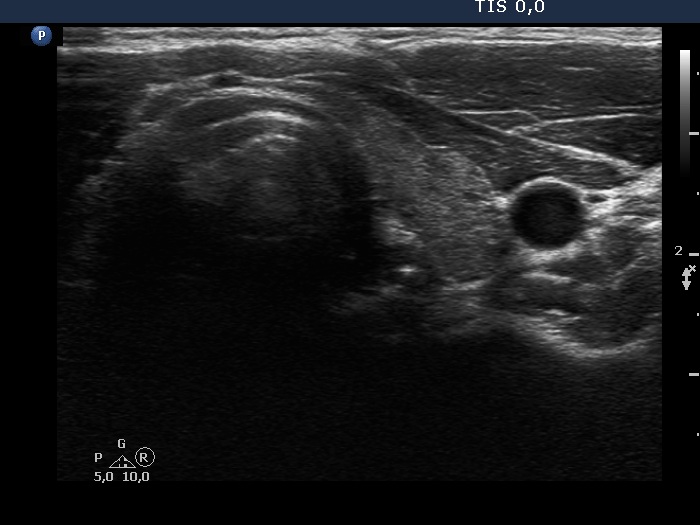

Parathyroid lesions - case 148 (ultrasonographic picture 6)

Right lobe, longitudinal scan

Left lobe, transverse scan. This lobe is minimally hypoechoic.